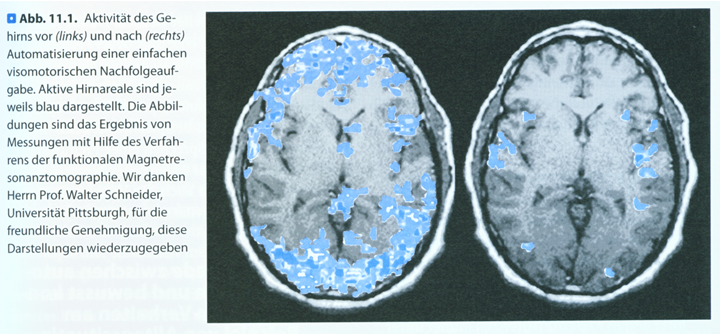

Automatisierung hat eine Steigerung der Verarbeitungsgeschwindigkeit im Gehirn von 1000% bis 2000% zur Folge und ermöglicht damit eine ungeheure Kapazitätserweiterung. („Positiv lernen“ Jansen und Streit / Seite 88)

Diese Abbildung ist mit freundlicher Genehmigung entnommen aus „Positiv lernen“ von Jansen/Streit Seite 87